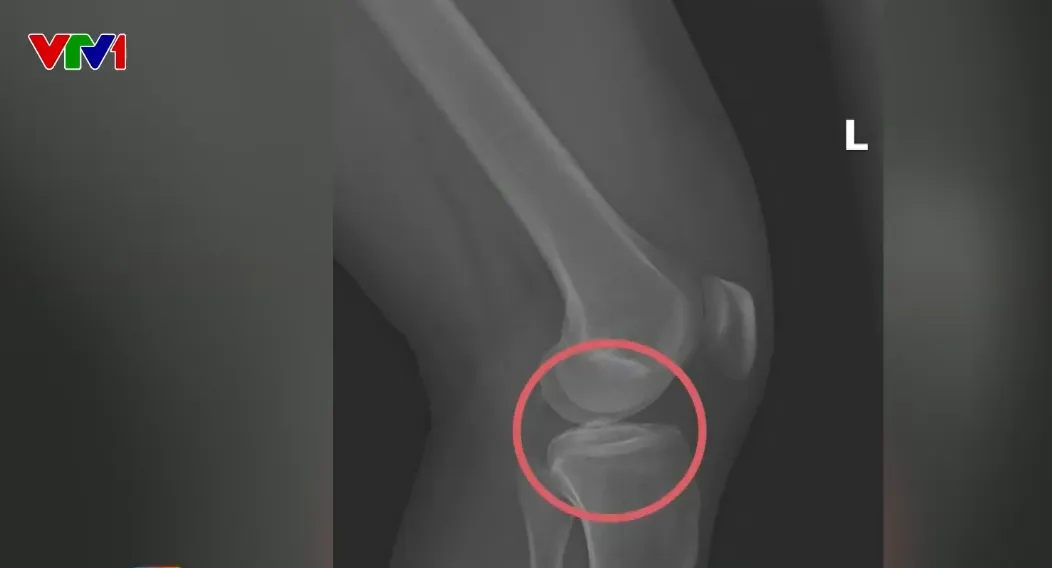

Hình ảnh chụp X-quang một số tổn thương xương do chính đối tượng cầm đầu gây thương tích. Hiện trường khu vực vắng vẻ, bỏ hoang, không có người dân sinh sống, cũng không có bất cứ trang thiết bị y tế nào tại đây. Các đối tượng tiến hành gây mê và can thiệp xương.

Hình ảnh chụp X-quang một số tổn thương xương do chính đối tượng cầm đầu gây thương tích.

Đối tượng trực tiếp thực hiện hành vi tiêm thuốc mê rồi dùng kim tiêm, búa để tác động vào xương người mua bảo hiểm, tạo nên các vết vỡ xương tương tự tai nạn thật.